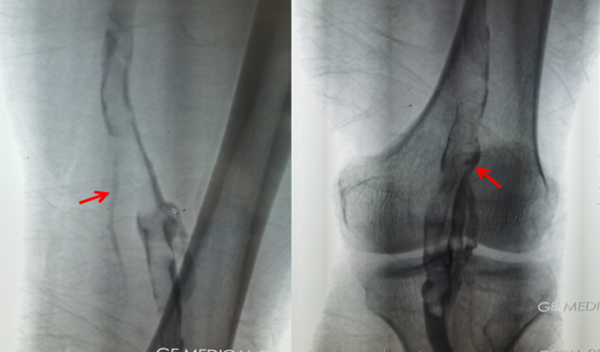

圖二:下肢造影示:右腘靜脈,股靜脈血栓

麻醉科迅速深靜脈置管,各類搶救藥品保障基本循環(huán)功能支持。血管外科行下肢靜脈造影示:左側腘靜脈股靜脈大量血栓形成,立即順利完成“下腔靜脈濾器植入術“。隨后,迅速麻醉誘導氣管插管消毒鋪巾,心臟外科立刻開胸,胸骨劈開后,患者出現(xiàn)心臟驟停。麻醉科手術室及心臟外科一邊胸內心臟按壓,一邊緊急建立體外循環(huán)。5分鐘后,體外循環(huán)順利工作,患者循環(huán)呼吸功能獲得支持。手術完整徹底取出左右肺動脈血栓,最長血栓長近20厘米,最粗直徑約1.5厘米。手術順利,術后4小時清醒,停呼吸機,拔除氣管插管。術后第二日轉入普通病房,術后第三天下床進行功能鍛煉。術后第七天,復查心臟超聲、肺動脈CTA 、生化常規(guī)等檢查提示手術結果滿意,各臟器功能正常,術后第十天患者順利康復出院。